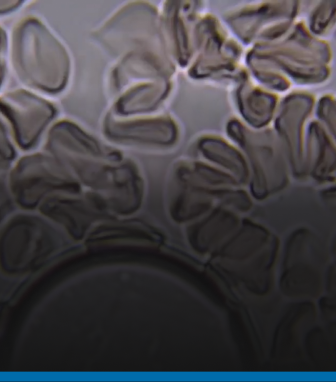

CARDIOVASCULAR DISEASE